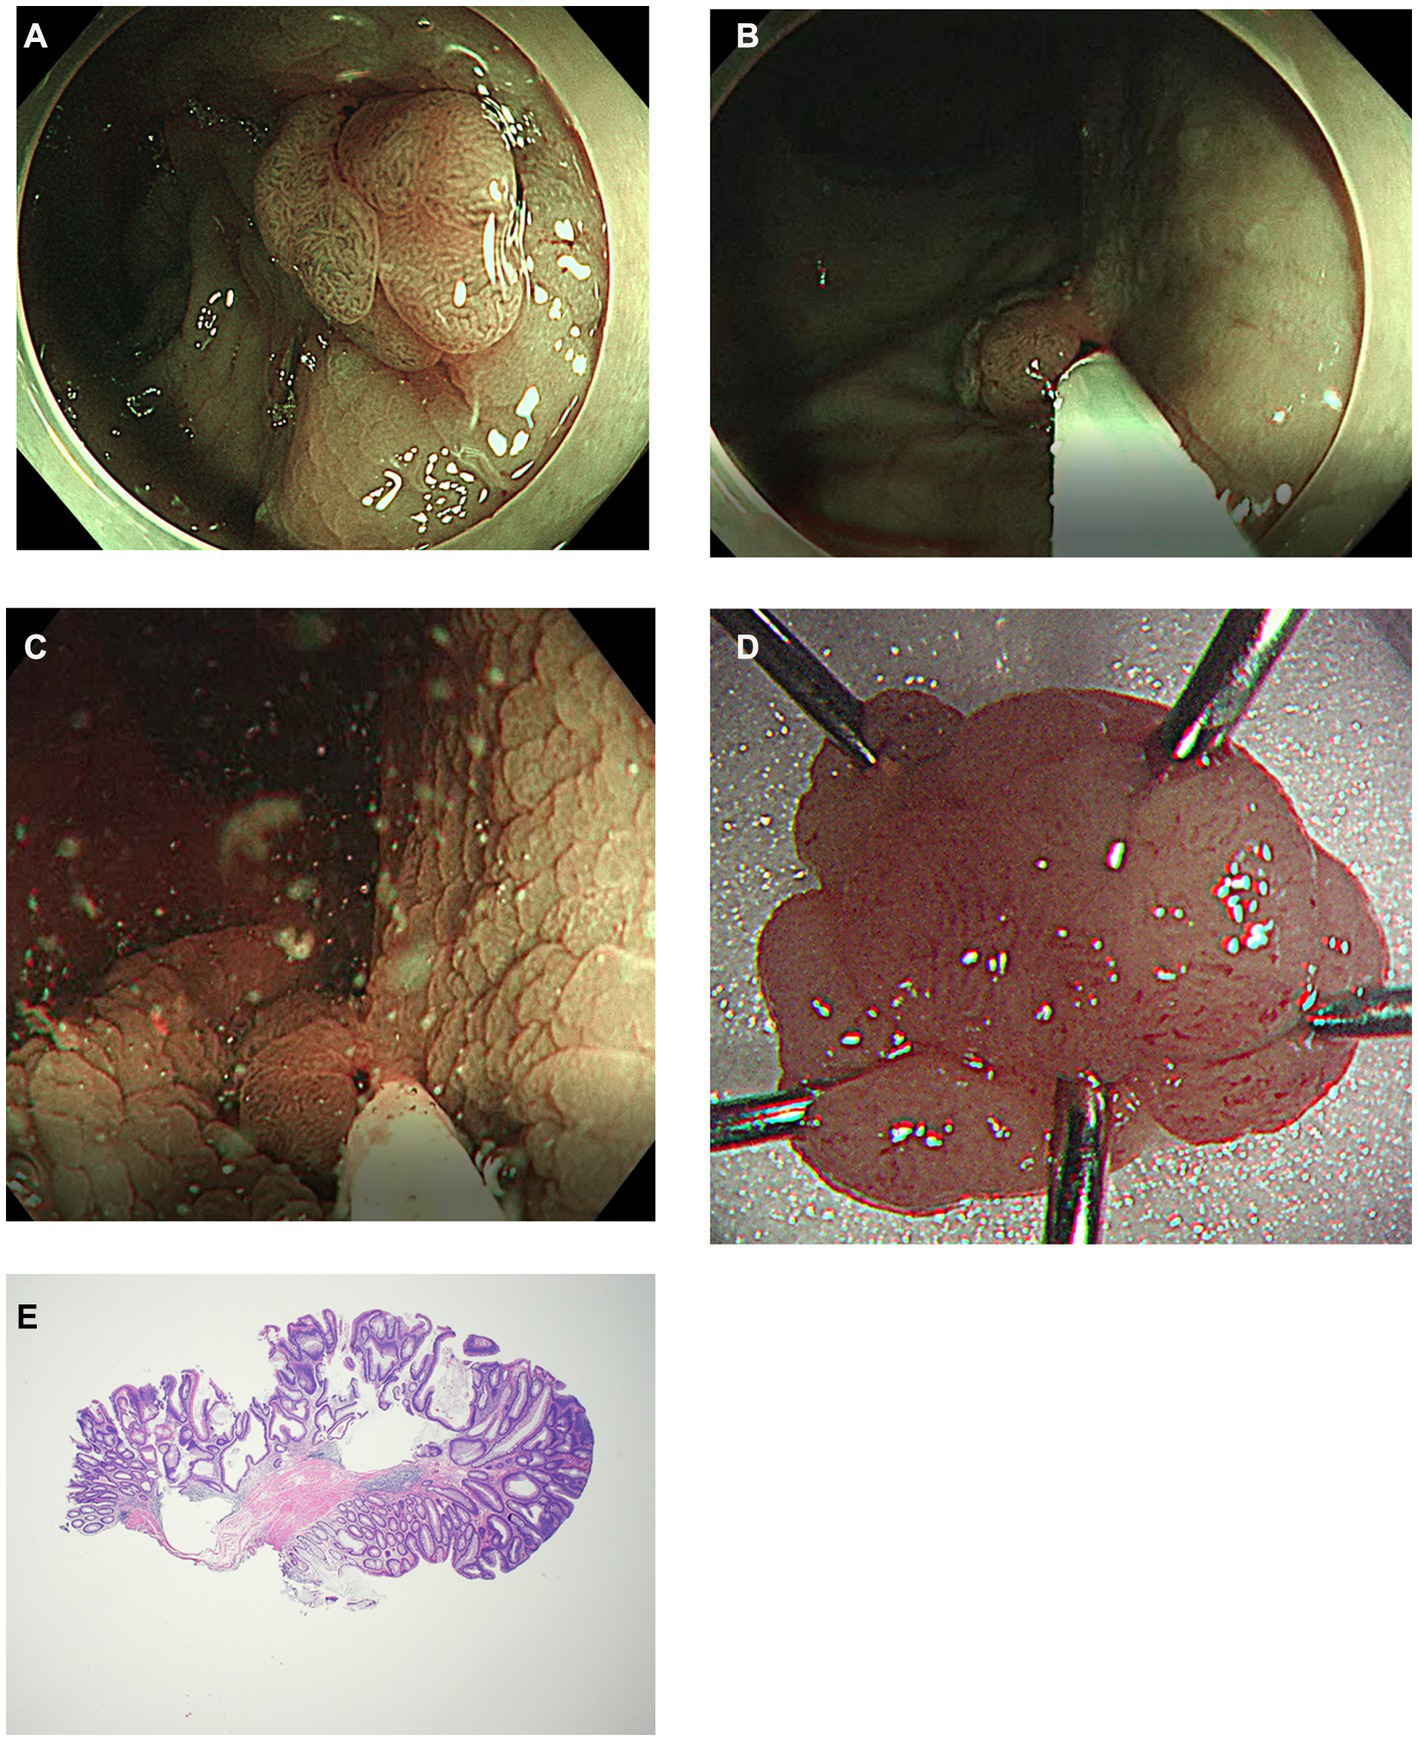

Figure 2

Another case of modified underwater endoscopic mucosal resection. (A) Endoscopic view of the 13 mm sized sessile colon polyp on rectum under narrow-band imaging. (B) Snaring the lesion and the surrounding mucosa without injection or water infusion. (C) Distilled water was injected using a water-jet pump until the lesion was submerged and excised using electrocautery. (D) Gross image of the completely removed colon polyp. (E) Histology of R0 resection of tubular adenoma with low grade dysplasia using modified underwater endoscopic mucosal resection. No definite evidence of muscularis propria entrapment was noted (×20).